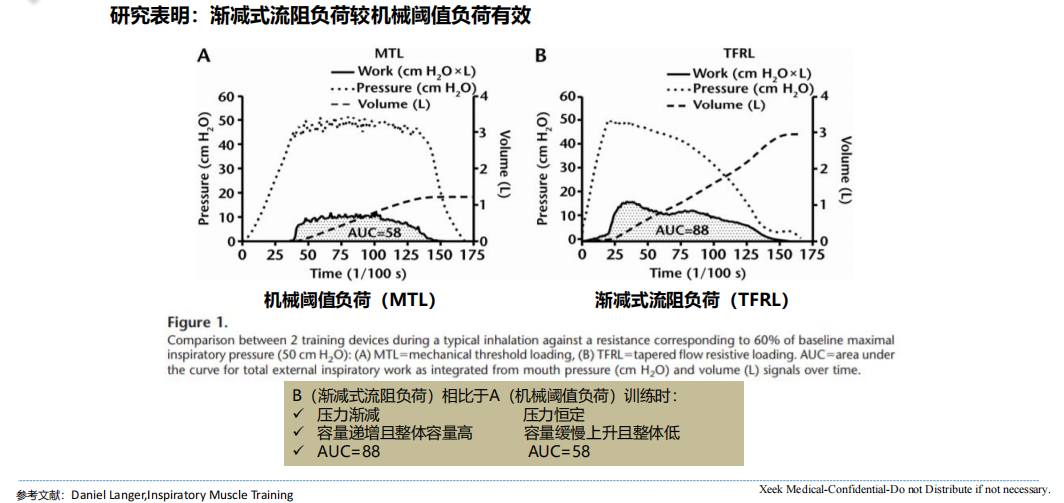

机械(xiè)阈值负荷呼吸训练器利用(yòng)恒定负载阻抗呼(hū)吸肌(jī)肉训练,主要(yào)是通过调节(jiē)弹(dàn)簧的长度来获取(qǔ)不同的阻抗,可获得恒定的阻力,即训练(liàn)时不管是快速吸气还是缓慢吸(xī)气,都有(yǒu)阻力(lì)的,保证使用者的训练是有效的,但当(dāng)吸气压力(lì)小于设置的阻力值(zhí)时,就无(wú)法进行训练。这(zhè)种恒定的负荷(hé)不适应呼(hū)吸系统的压力-容量关系(随着吸气时肺容量的逐渐增加(jiā),吸气流(liú)速(sù)和压力(lì)逐渐减小),会限制容量反应,影(yǐng)响呼吸肌在收缩过程中(zhōng)能刺激的长度,使其不能很好(hǎo)地训练到(dào)呼吸肌。目前是市面上的机械阈值负荷呼吸训练器多为(wéi)机械(xiè)款,部分(fèn)为电子式,可搭配App/PC软(ruǎn)件使(shǐ)用。

03 渐减式流阻负荷呼吸训练器

渐减(jiǎn)式流阻负荷也称(chēng)为锥形流阻(zǔ)负荷,该(gāi)款呼吸训练器(qì)结(jié)合(hé)了机械阈值负荷和目标流阻(zǔ)负荷的特(tè)性,利用流量压力传(chuán)感器(qì)控制(zhì)阀门(mén)开(kāi)口大小,可以(yǐ)对(duì)呼吸气流产(chǎn)生阻力,实现对呼吸气流的负载阻抗。

渐减式流(liú)阻呼吸训练(liàn)器开阀门的(de)数值是起始数值,这个值是(shì)固定值,因此刚(gāng)开始训练(liàn)时需要(yào)产生一定的压力克服阈值(zhí)负荷从而打(dǎ)开阀门,也就训练初要尽可能快速、用力吸气/呼气;当阀门(mén)打开(kāi)后(hòu),阻抗就变(biàn)为动(dòng)态(tài)的,并随(suí)着(zhe)吸(xī)气/呼气(qì)压力(lì)的(de)逐渐(jiàn)降低而渐减。渐减式流(liú)阻负(fù)荷的训练方式适应了呼吸系统的压力(lì)-容量(liàng)关系,在相同阻力(lì)下,使用渐减式流阻负荷(hé)训(xùn)练,可以使吸气容量更高,且阻(zǔ)抗伴随整(zhěng)口气,这样不仅(jǐn)大大减(jiǎn)少呼吸肌损伤,也达到训练的最佳效果。目前市(shì)面上的渐减(jiǎn)式流阻(zǔ)负荷呼吸训练器大多(duō)可(kě)搭配App/PC软件使(shǐ)用,不(bú)少研究表明渐(jiàn)减式流(liú)阻负荷训练较目标流阻负荷训练、阈(yù)值负荷(hé)训练效果更佳。